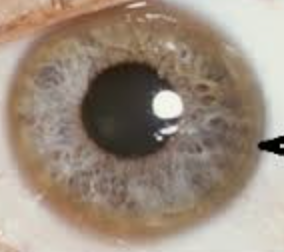

Frequent changes in Rx, hx of eye rubbing, progressive reduction of BCVA. ghost image/monocular diplopia, hx of asthma/allergies/atopia

Keratoconus: non inflammatory, progressive thinning and bulging into a cone-like shape, causing distorted vision.

Objective:

Early signs: Fleischer ring, scissor reflex, inferior steepening

Late: Vogt’s Striae, Hydrops, Munson sign, Rizzuti sign

Mild: <48D, Mod: 48-54D, Severe: >54